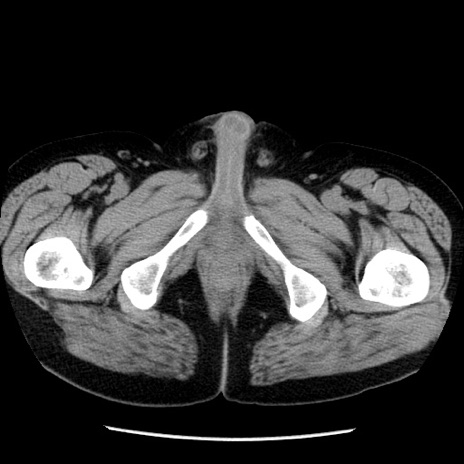

症例29(横断像)

【症例】40歳代男性

【現病歴】2日前から胃痛あり。徐々に周期的な激痛に変化した。本日になっても激痛があるため受診。

【身体所見】意識清明、BT 38-39℃台あり、腹部:膨満、やや硬、右下腹部に圧痛あり。

【データ】WBC 8500、CRP 23.26